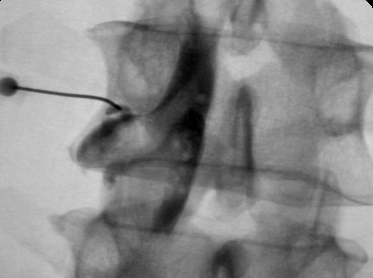

В трудных для диагностики случаях можно дополнительно к МРТ позвоночника применить дискографию, которая достоверно подтвердит или опровергнет диагноз рецидивной грыжи диска. Эпидурография также может быть полезна для оценки состояния корешка в позвоночном канале.

![]()

Фораминальная рецидивная грыжа 5 мм. Дискография.

Сдавление корешка L4 в корешковом канале, несмотря на малые размеры грыжи. Эпидурография.